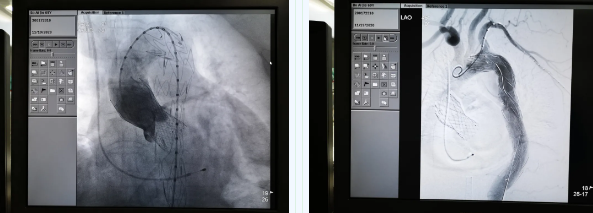

11月19日,西安國際醫(yī)學(xué)中心醫(yī)院心臟外科TAVR團(tuán)隊(duì)在心臟病醫(yī)院張金洲副院長主持下,順利完成一例罕見“經(jīng)股經(jīng)導(dǎo)管主動(dòng)脈瓣置換術(shù) 經(jīng)導(dǎo)管主動(dòng)脈腔內(nèi)隔絕術(shù)”。經(jīng)查閱文獻(xiàn)證實(shí),此一站式復(fù)合手術(shù)國內(nèi)尚未見報(bào)道。由此,西安國際醫(yī)學(xué)中心醫(yī)院心外團(tuán)隊(duì)在心臟微創(chuàng)治療領(lǐng)域又向前邁進(jìn)了一大步。

張金洲副院長關(guān)注著手術(shù)的每一個(gè)細(xì)節(jié),從建立軌道、跨瓣、釋放瓣膜、支架定位、造影和食道超聲確認(rèn),每一步都緊張而有序地進(jìn)行著。為了最大程度保障病人安全,心臟外科程亮副主任也帶隊(duì)建立動(dòng)靜脈入路,以備緊急體外循環(huán)。經(jīng)過團(tuán)隊(duì)每一位成員的密切配合,在近四小時(shí)的緊張奮戰(zhàn)之后,“TAVR TEVAR”復(fù)合手術(shù)順利完成;經(jīng)過造影和食道超聲證實(shí):人工主動(dòng)脈瓣無返流無瓣周漏、冠脈顯影良好,主動(dòng)脈覆膜支架無內(nèi)漏無移位。